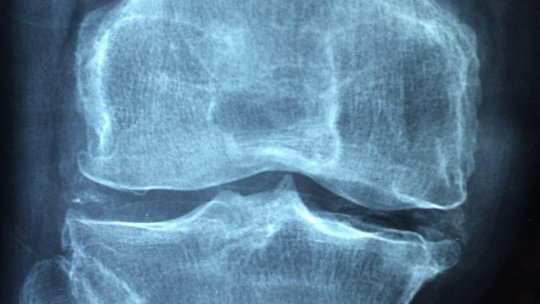

Cartilajul uzat și inflamația provoacă rigiditate și durere la nivelul articulațiilor. Osteoartrita și artrita sunt forme...